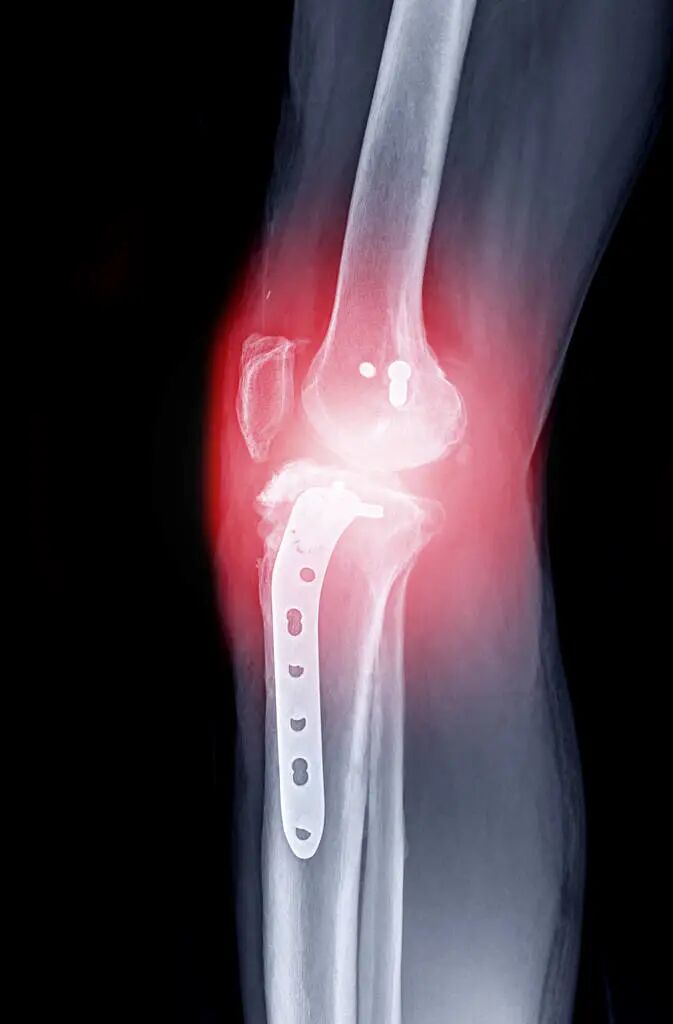

肥胖不仅会影响人们的体形,还会对健康造成很大的危害。其中一个危害就是对关节造成损伤。肥胖者每步走路都要承受2-3倍于正常人的重量,因此容易造成关节疼痛、滑动、强直。

由于关节处于不断移动和承受压力的状态,这样的情况会逐渐加剧关节损伤,导致关节炎、骨刺形成等问题。

当你年纪大了,关节就会变得越来越脆弱。如果你经常扛重物上下楼,这些关节就会受到过度的负荷。长此以往,这些关节就会逐渐变形,最终导致关节炎。正因为如此,老年人是最容易得关节炎的人群。